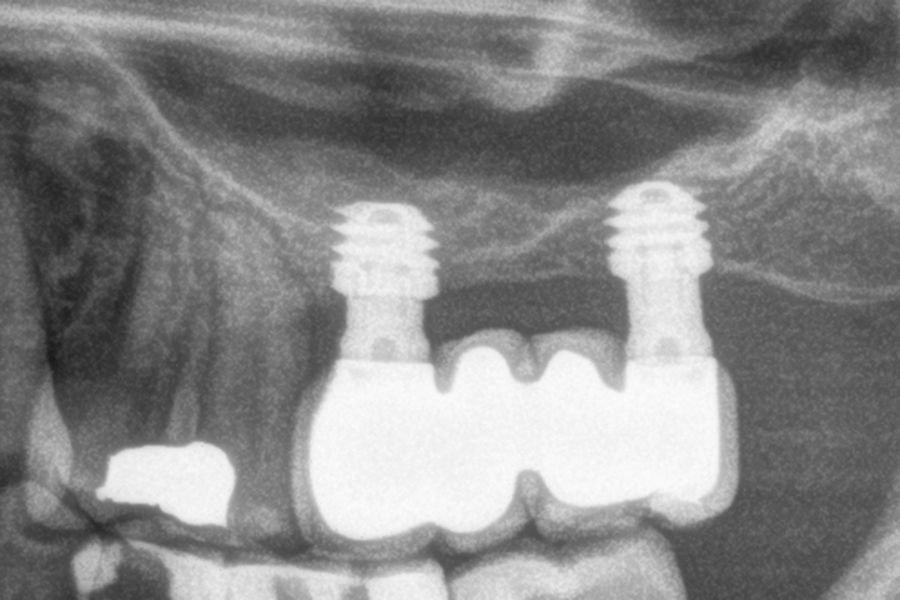

Figures 2-19 show one of the cases included in the study.

All implants were rehabilitated in two phases and all of them were ferulized to other implants in the rehabilitation. In all cases, screwed prostheses of more than one implant with intermediate elements (transepithelial) were performed, ferulizing to other implants with a length of 4.5 or 5.5 mm. In all situations, a progressive prosthesis load was carried out 6 months after insertion of the implant consisting of a provisional structure finished in resin to move to a definitive metal-ceramic prosthesis. In all cases, the initial transepithelial are preserved to maintain the hermeticity achieved in the first phase of prosthesis manufacture.

The mean height of the residual bone volume was 3.1 mm (+/- 0.3 mm with a range of 3-4 mm). In all cases, transcrestal sinus elevation was performed, with particulate autologous bone obtained from milling the neo alveolus generation zone for implant insertion, being the average of this elevation above the apex of the implant of 2.8 mm (+/- 0.99 range 1.9 -5 mm). In the CT control scan after one year of inserting the studied implants, the bone gain achieved was maintained, no decrease in the volume gained was observed, only three cases showed a decrease of between 0.4 and 0.5 mm of the initial volume at the end (Table).